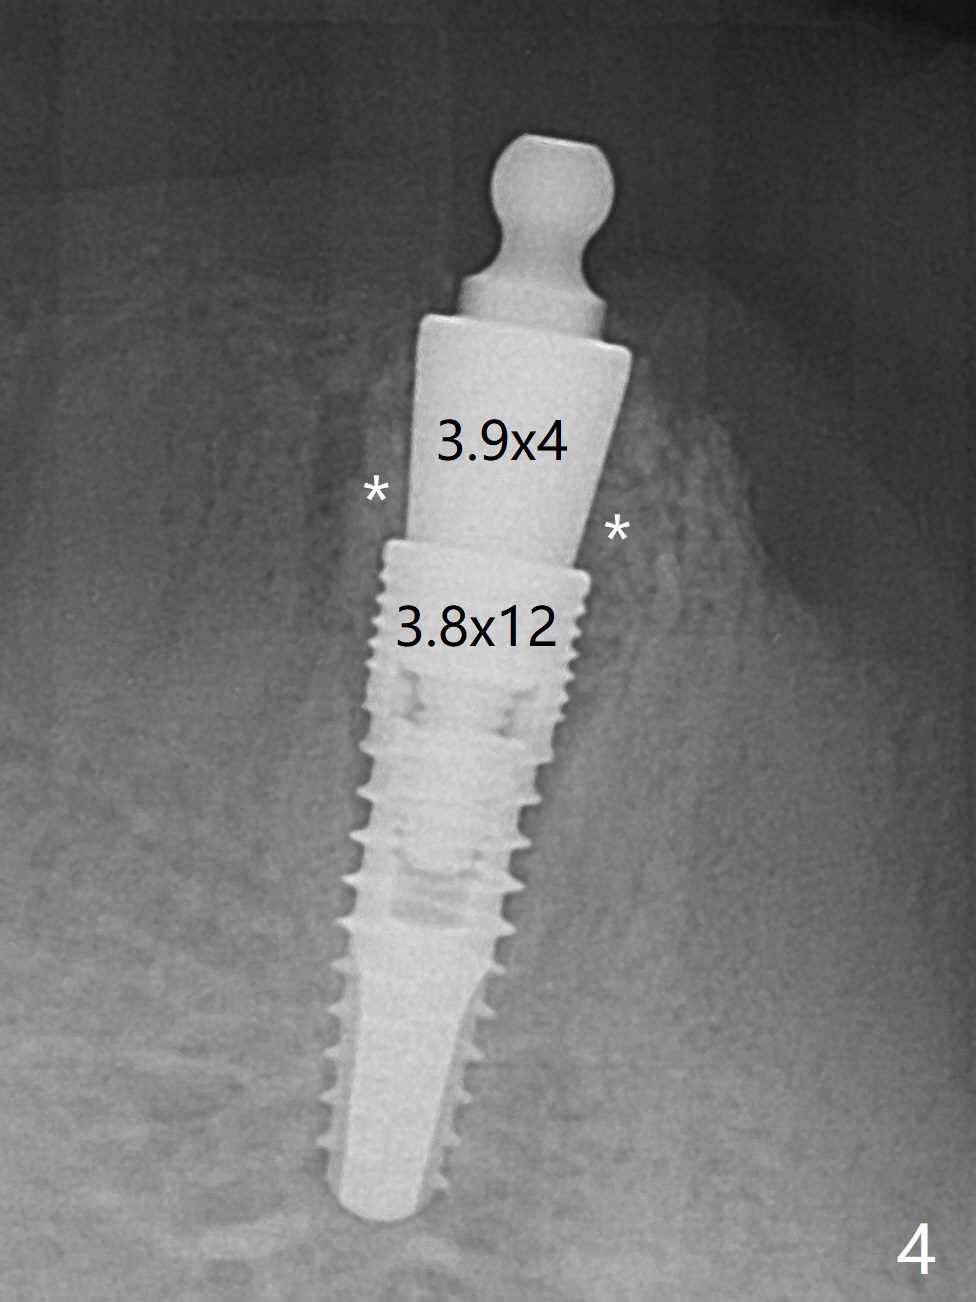

The ridge at #27 is narrow and is reduced ~ 4 mm in height (Fig.1 *) to obtain ~ 4 mm buccolingual width. A 3x14 mm 1-piece implant with ball abutment is placed (Fig.3 (*: bone graft)). In contrast, there is no problem of the buccolingual width after #22 extraction; initial osteotomy depth is 14 mm to gain ~ 5 mm of the native bone for primary stability (Fig.2). Since the lingual crest is significantly lower than the buccal one, a shorter implant (2-piece, 3.8x12 mm, Fig.4) is placed so that a ball abutment with a longer cuff is chosen (4 mm). Soft reline is applied to the site of #22 with minimal retention. But the patient is pleased with the "pain-free" procedure. It appears that gingivectomy is required for the ball abutments in 2 months (Fig.5). The implants seem osteotointegrated nearly 4 months postop (Fig.6,7). Ten months postop, the patient will return for fabrication of new full dentures to correct Class II relationship. There is mild or no bone loss 2 year 4 months postop (Fig.8,9), although the housing at #27 is dislodged. Return to Lower Canine Immediate Implant, Armaments Overdentures Xin Wei, DDS, PhD, MS 1st edition 07/24/2018, last revision 12/18/2020